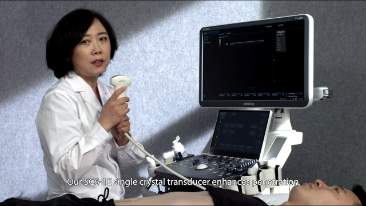

Mindray Resona Genel G?rĂŒntĂŒleme ??zĂŒmleri, kapsaml? alt b?lĂŒm uygulama problar? ve verimli klinik uygulama ara?lar? arac?l???yla, klinisyenlerin daha do?ru ve verimli tan? ve tedavi sonu?lar? elde etmesine yard?mc? olur.